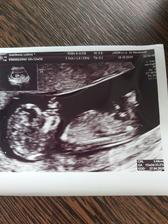

Druhé šťastie